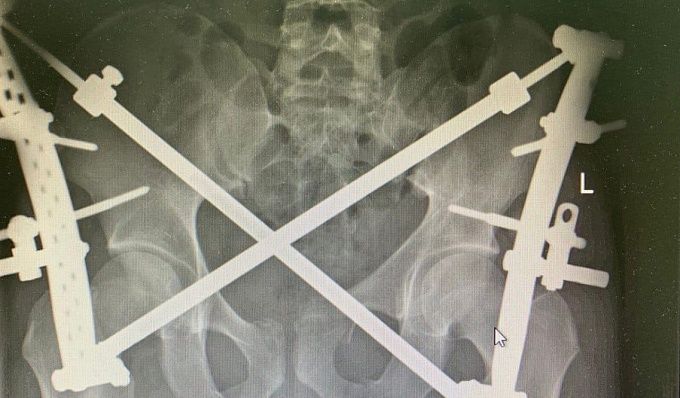

Позже медики выставили диагноз: сочетанная травма, политравма. Множественные закрытые переломы костей таза, ребер, обеих голеней и стоп.

– Всего за время нахождения в больнице мужчине выполнили четыре поэтапных оперативных вмешательств. В самом обширном из них, по остеосинтезу костей таза, было задействовано одновременно четыре травматолога, два анестезиолога. Специалистам необходимо было анатомически точно сопоставить фрагменты поврежденных костей, а затем зафиксировать специальными имплантами, – добавили в РКБ.

Специалисты отметили, что подобные объемные операции могут сопровождаться большой кровопотерей (в данном случае мужчина потерял 800 мл). В связи с этим врачи использовали аппарат аутотрансфузии крови – кровь пациента проходило фильтрацию и внутривенно поступало обратно, тем самым, исключая необходимость в донорской крови.